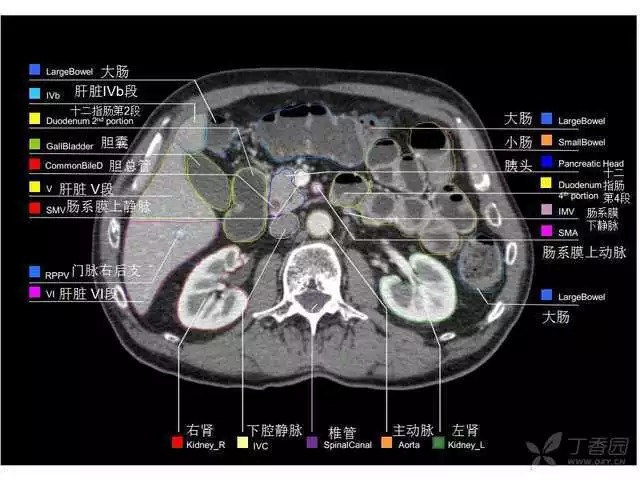

腹部肝脏高清CT断层的图谱

全腹部高清CT图谱,淋巴结彩色图谱,血管解剖图谱大汇总!

超声肝脏分叶及分段

肝脏分段和基本解剖学标志